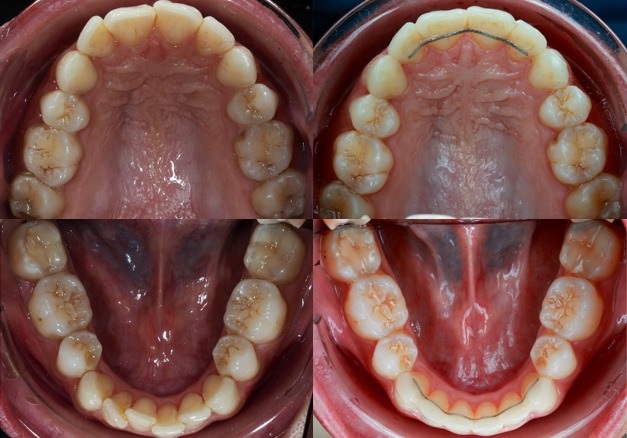

Photos Endobuccales :

Empreintes physiques ou numériques :